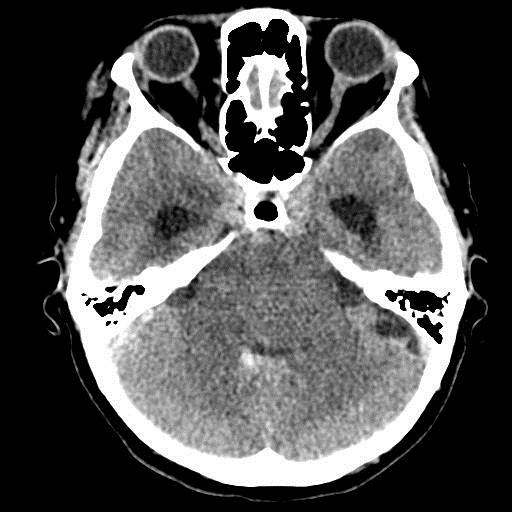

КТ головного мозга, кровоизлияние.

"Скорая" привезла женщину 75 лет, найденную на улице. На КТ направлена с д-зом: кома неясного происхождения. Вот такая картина на КТ.

Острое внутримозговое кровоизлияние с выходом крови в желудочки (боковые - сгустки преимущественно в левом + эффект седиментации с горизонтальным уровнем жидкость\жидкость в задних рогах; сгустки крови в третьем желудочке, кровь в четвертом). Значительное увеличение височных рогов боковых желудочков - гидроцефалия. Смешение срединных структур вправо, отек белого вещества перивентрикулярно слева.

Довольно большие кровоизлияния в стволе мозга (что объясняет тяжесть состояния).

Дифференциация серого и белого в-ва сохраняется, хотя субарахноидальное пространство не прослеживается - проявление масс-эффекта, начальный этап отека мозга.

Про отек: субарахноидальных щелей совсем нет, по белому веществу и в стволе снижение плотности, извилины утолщены, серое вещество на этом фоне выглядит более светлым, толстым, подушкообразным.

Кровоизлияние не связанное с объемным образованием, "гипертоническое", основной массой - в области базальных ядер, кровоизлияние в ствол мозга, кома ясного происхождения :) А менингиома менигниомой, не мешает, так сказать.  Отека мозга здесь небольшой, больше выражено набухание.